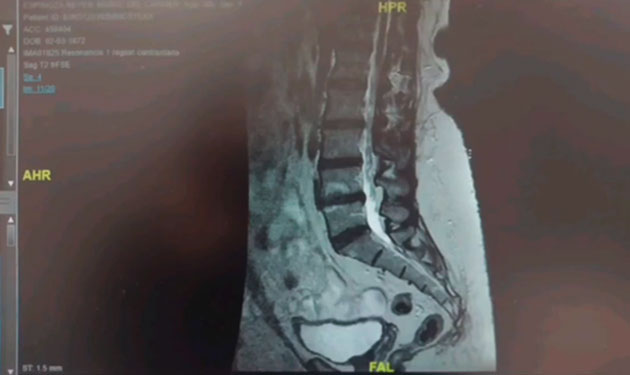

Radiofrecuencia en tratamiento de hernias discales.